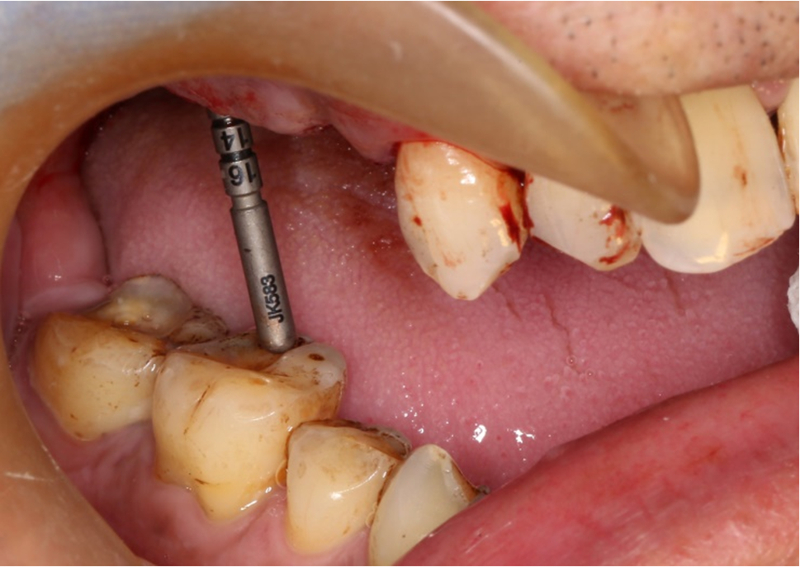

®按照術前方案進行備洞及植體植入

®按照術前方案進行備洞及植體植入,醫(yī)生可以通過屏幕軟件引導對手術中植入點、角度、深度實時追蹤

®對植體深度及方向進行確認